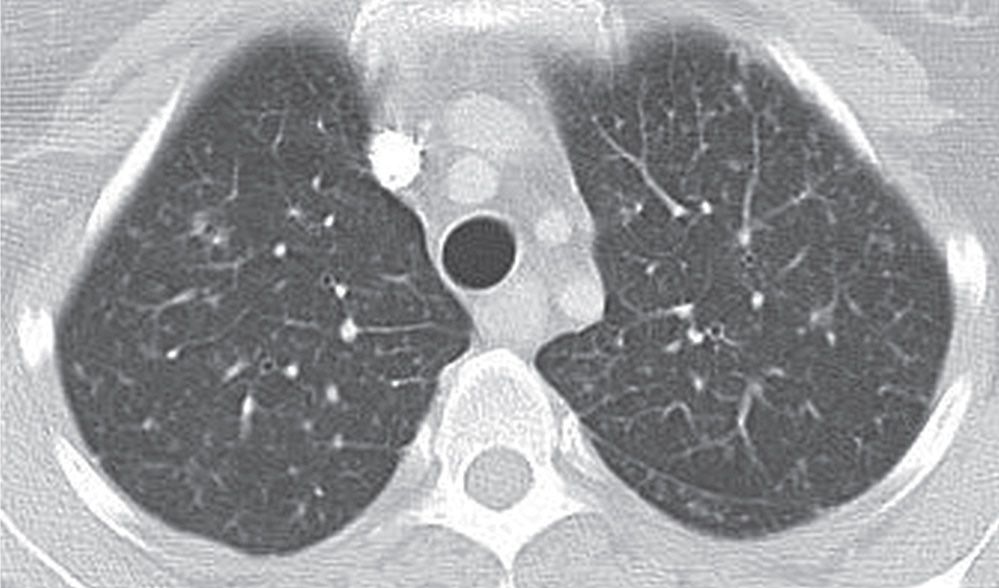

UIP pattern interstitial lung disease in rheumatoid arthritis Image

UIP pattern interstitial lung disease in rheumatoid arthritis Image Ild Radiology Hrct Radiology department of the rijnland hospital, leiderdorp and the academical medical centre, amsterdam, the netherlands. Learn about the recommended protocol for evaluating ild on hrct, including important aspects of writing the order for an. Click here to learn more about the role of high resolution computed tomography (hrct) in diagnosing interstitial lung disease. Hrct plays an important role in the. Ild Radiology Hrct.